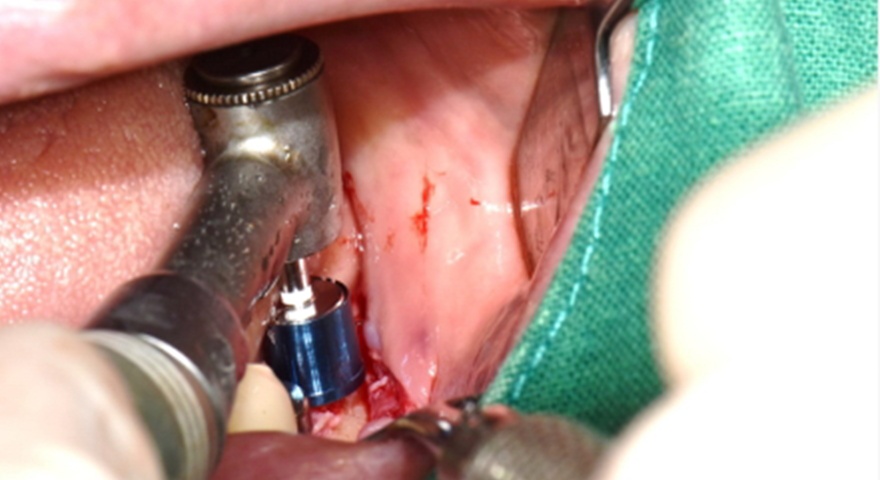

Після проведення стандартної імплантації в ділянках з оголеною різьбою було застосовано техніку DUK: на імплантат наносили спочатку пастоподібний матеріал, далі — гранули, після чого укладали мембрану та закривали клапті швами без натягу. Всі пацієнти отримували антибіотики (амоксицилін) та знеболення (ібупрофен), а через шість місяців — проходили контроль та біопсію ділянки.

Рис. 2. (A) Пацієнт із виявленою необмеженою (non-contained) втратою кісткової тканини та оголенням імплантату з букального боку на момент встановлення імплантату. (B) Нанесення основного шару пастоподібного кісткового матеріалу перед внесенням гранульованого кісткового трансплантата. (C) Укладання колагенової мембрани з покриттям зони трансплантації — від букального до піднебінного боку — та фіксували за допомогою внутрішніх періостальних швів. (D) Через шість місяців після аугментації — візуалізується регенерація кістки з букального боку в ділянці раніше оголеної різьби імплантату.